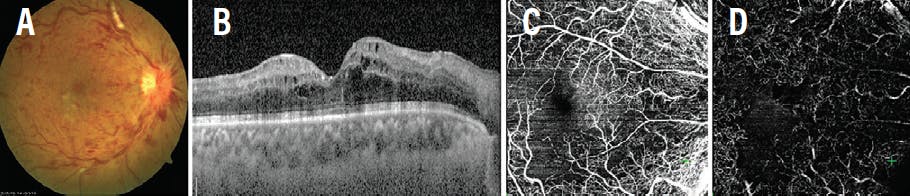

A 64-year-old man with hypertension presented with blurred vision in the left eye for 1 day and BCVA of 20/60 OS. Fundus examination showed advanced cupping in each eye and a well-defined parafoveal, intraretinal, grayish lesion with characteristic OCT features suggestive of PAMM (Figure 7A and 7B). Visual field analysis confirmed glaucomatous damage, and the patient was started on medication for primary open-angle glaucoma. The patient presented 3 days later with deterioration of vision to hand movement OS (Figure 7C and 7D). A diagnosis of CRVO with CME and possible central retinal artery hypoperfusion was made based on the findings.

The patient was started on monthly injections of ranibizumab. After 3 months, his VA improved to 20/200, with resolution of the macular edema (Figure 7E and 7F).

<p>Figure 7. The fundus photograph of this glaucomatous eye shows a perifoveal intraretinal greyish lesion (A), and the corresponding OCT shows hyperreflective band-like lesions in the middle retinal layers of the macula, suggestive of PAMM (B). Fundus photography of the same eye 3 days later shows dilated tortuous vessels with diffuse intraretinal hemorrhages (C), and the corresponding OCT shows macular edema (D). After three anti-VEGF injections, the fundus photograph (E) and OCT (F) show resolution of CRVO and macular edema.</p>

Figure 7. The fundus photograph of this glaucomatous eye shows a perifoveal intraretinal greyish lesion (A), and the corresponding OCT shows hyperreflective band-like lesions in the middle retinal layers of the macula, suggestive of PAMM (B). Fundus photography of the same eye 3 days later shows dilated tortuous vessels with diffuse intraretinal hemorrhages (C), and the corresponding OCT shows macular edema (D). After three anti-VEGF injections, the fundus photograph (E) and OCT (F) show resolution of CRVO and macular edema.